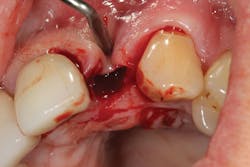

Because of this alveolar resorptive pattern after tooth extraction, bone grafting the extraction socket after tooth extraction procedures has become a solution that attempts to limit the amount of hard- and soft-tissue loss. There are many systematic reviews in the literature that compare the results of residual ridge dimension following tooth extraction after the use of a bone graft (with or without a membrane) versus extraction alone without grafting.7

• site development to increase hard and soft tissue for pontic sites in fixed bridge prosthetics (figures 9–14);• correcting bone defects impinging upon anatomical structures after tooth extraction, such as oroantral communication (figure 18); and

• preserving tissue structure for subsequent dental implant therapy.Decision matrix